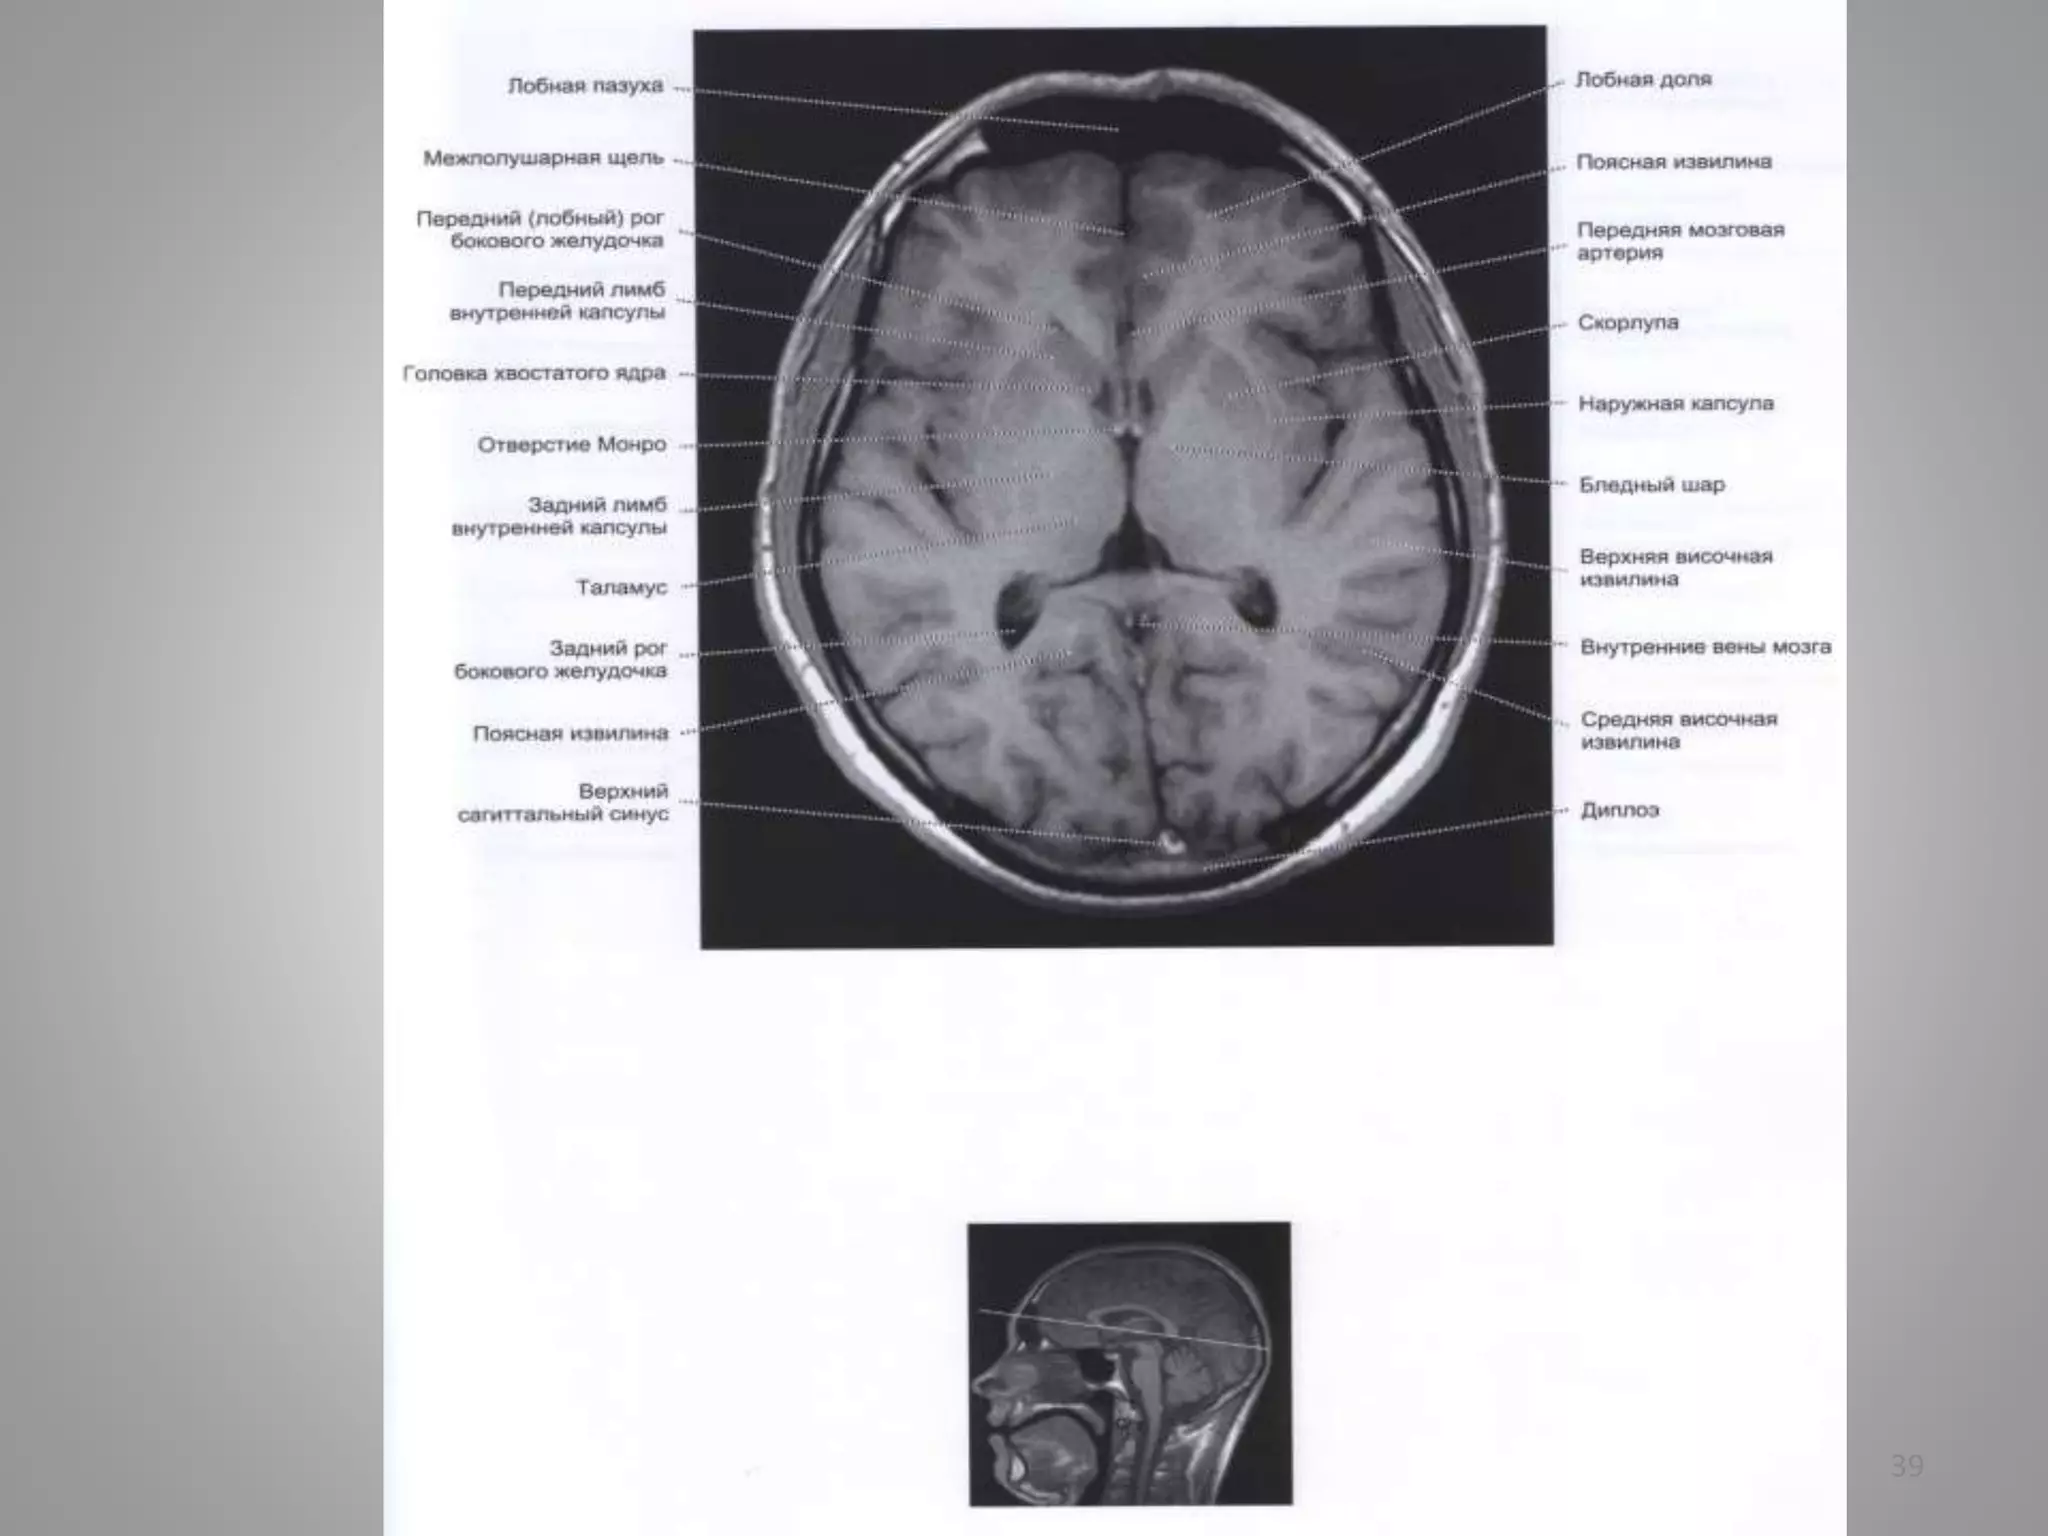

МРТ хворого із нормотензивною

гідроцефалією (сполучною)

• Рис. А. Аксіальний зріз у Т2-режимі. Рис. В. Фронтальний зріз.

• Шлуночки непропорційно збільшені відносно субарахноїдального

простору.

• Зображення недостатньо чіткі внаслідок рухів хворого: такі пацієнти

часто унаслідок асоційованої деменції неспроможні лежати нерухомо

під час сканування.